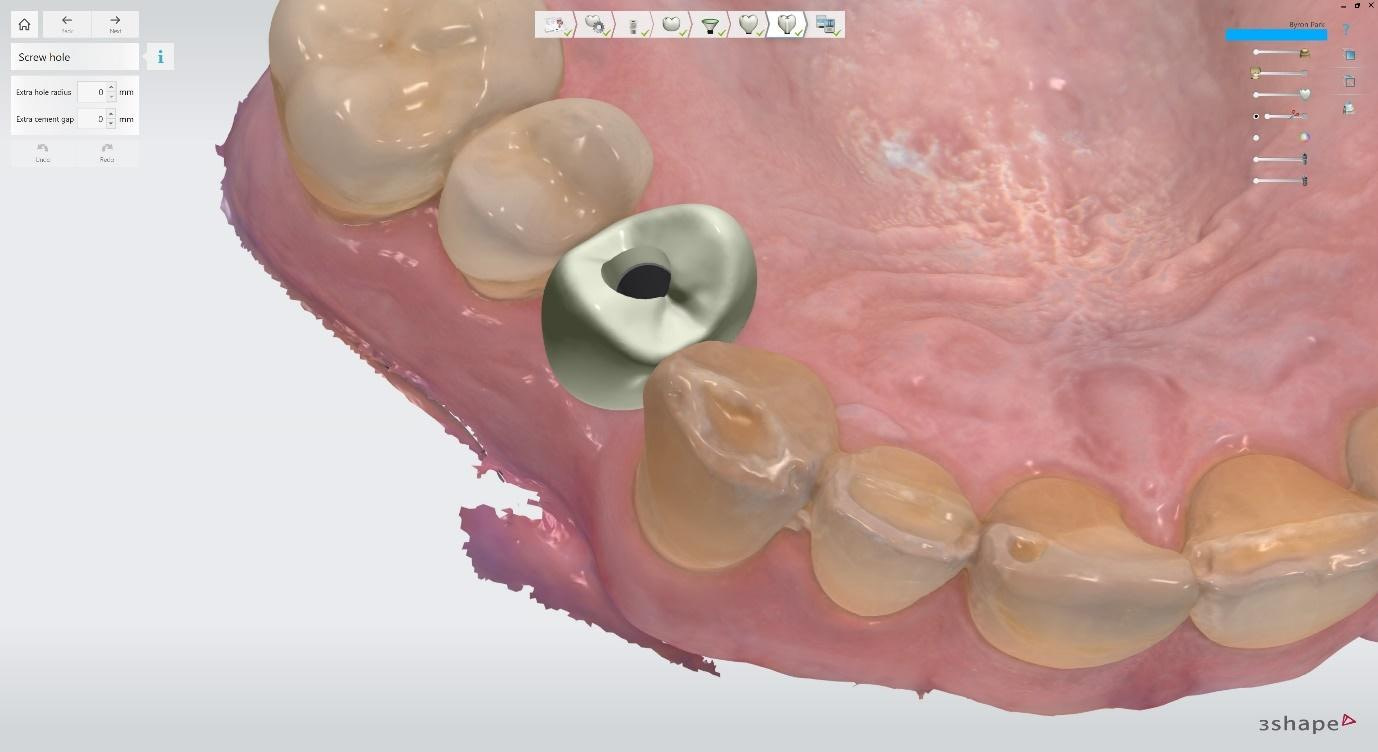

Digital impressions were captured using the TRIOS 4 intraoral scanner, and the implant-supported crown was designed using 3Shape Design Studio.

Implant detection matches the scan body in the intraoral scan with the digital library. A colour scale is given to show the accuracy of the matching (Green is good).